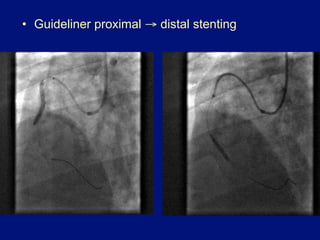

•  Guideliner proximal → distal stenting

•  Guideliner proximal→ distal stenting